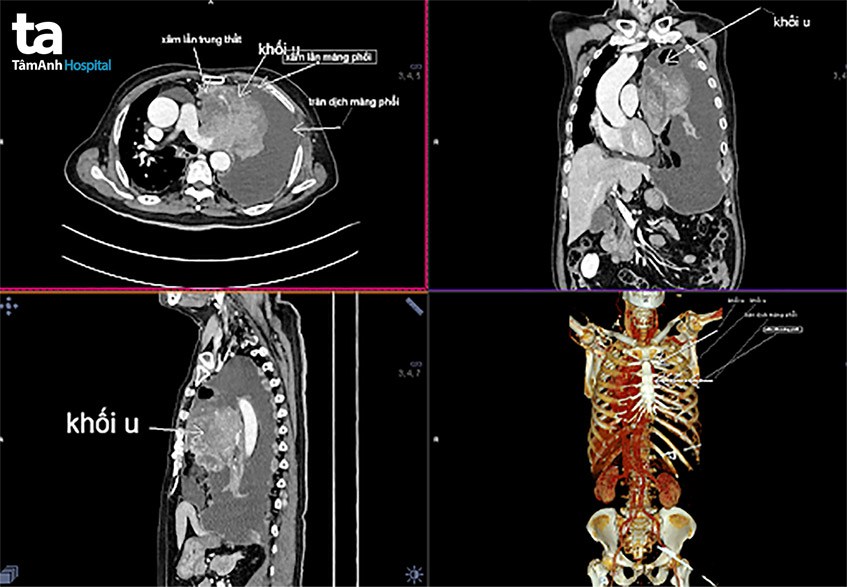

Không may mắn như anh V.K, ông M.T (76 tuổi, Q.Phú Nhuận) vốn không có tiền căn bệnh gì đặc biệt. Ông luôn tuân thủ lịch khám sức khỏe định kỳ 6 tháng/lần. Đến khi thành phố thực hiện giãn cách xã hội, ông trễ hẹn tái khám gần một năm nay. Khi các dấu hiệu bệnh xuất hiện, ông cũng ngần ngại đến bệnh viện. Khi ông bắt đầu cảm thấy khó thở, thở nặng nhọc, có dấu hiệu suy hô hấp, gia đình vội vàng đưa ông đến bệnh viện thì đã muộn. Bác sĩ cho biết ông bị ung thư phổi giai đoạn cuối, tràn dịch màng phổi bên trái lượng lớn, hạch trung thất lớn ngay sau khí quản, di căn hủy xương sườn, di căn hủy thân đốt sống. Các phương pháp điều trị lúc này không thể chữa khỏi bệnh hoàn toàn, mà chỉ có thể làm giảm nhẹ triệu chứng của bệnh và kéo dài thời gian sống.